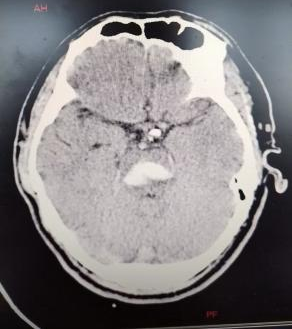

患者李先生于11月5日因“突发昏迷1小时”被紧急送入东海县人民医院急诊抢救室。经头颅CT检查,确诊为凶险的“脑干出血”。入院后,患者病情急速恶化,出血量增多,自主呼吸变得微弱,生命垂危,随即被转入ICU并进行气管插管,依靠呼吸机维持生命。

为确保万无一失,朱龙主任团队术前进行了全面的评估和精密的设计。他们利用先进的三维重建技术,将患者的头颅CT数据转化为立体模型,为李先生“量身定制”了个性化的手术方案和3D打印导航导板。该导板能在术中与患者头部完美贴合,如同为医生配备了“北斗导航系统”,确保穿刺路径精准无误,最大程度避开重要神经和血管,将手术创伤降至最低。

手术当日,在朱龙主任的带领下,神经外科团队与影像科、手术室等多科室紧密协作,凭借丰富的临床经验和精湛的操作技巧,在3D打印导板的实时引导下,将穿刺针精准置入脑干深部的血肿腔内,并成功抽吸血肿,有效解除了对生命中枢的压迫。